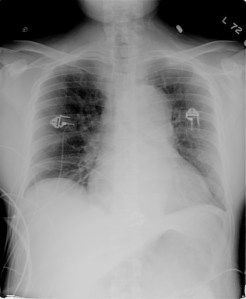

- Chest radiograph may show “boot shaped heart” and right aortic knob

“boot shaped heart” Case courtesy of A.Prof Frank Gaillard, Radiopaedia.org. From the case rID: 8049